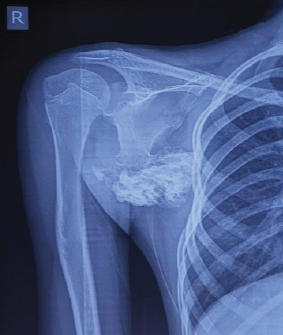

Undifferentiated Pleomorphic Sarcoma with Dual Smooth-Muscle and Osteogenic Differentiation Mimicking Plasma Cell Dyscrasia: A Rare Diagnostic Pitfall

Arnav P Rathod , Hrishikesh S Saodekar , Yogesh B Rathod , Rajendra Baitule , Ganesh Pundkar

………………………………p.262-266